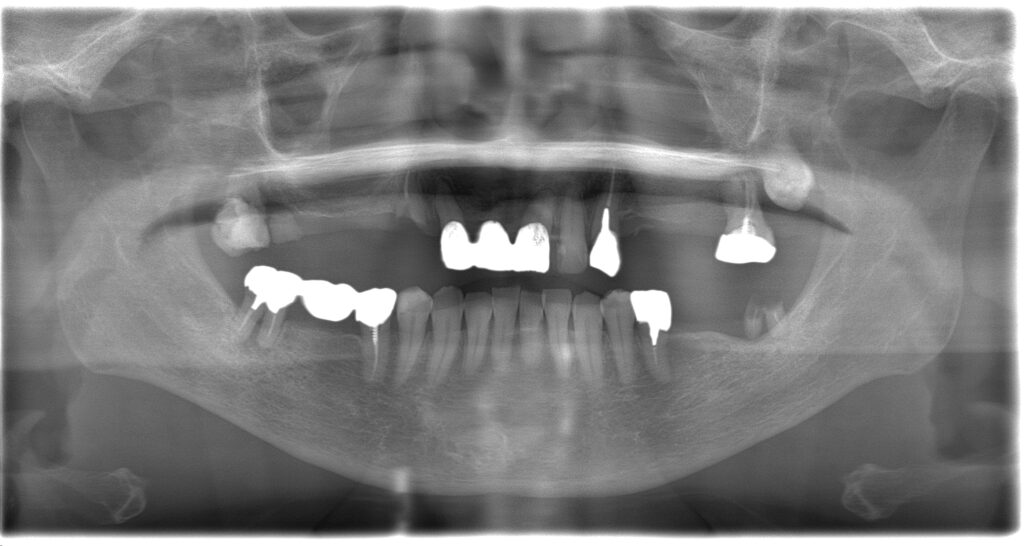

BEFORE

主訴

全体的に見た目を綺麗にしたい。奥歯でしっかり噛みたい。

診断名・主な症状

臼歯部欠損

年齢

70歳

治療内容

インプラント埋入(右上4・6,左上4・6,右下6,左下6)

ジルコニアBr(右上3―左上3)

ジルコニア(右下5,左下5)

治療期間/

通院回数

インプラント 1年5ヶ月/13回

ジルコニアBr、ジルコニアクラウン 3ヶ月/10回

費用

インプラント: 2,552,000円

その他治療: 640,000円

合計 3,192,000円

*いずれも税込